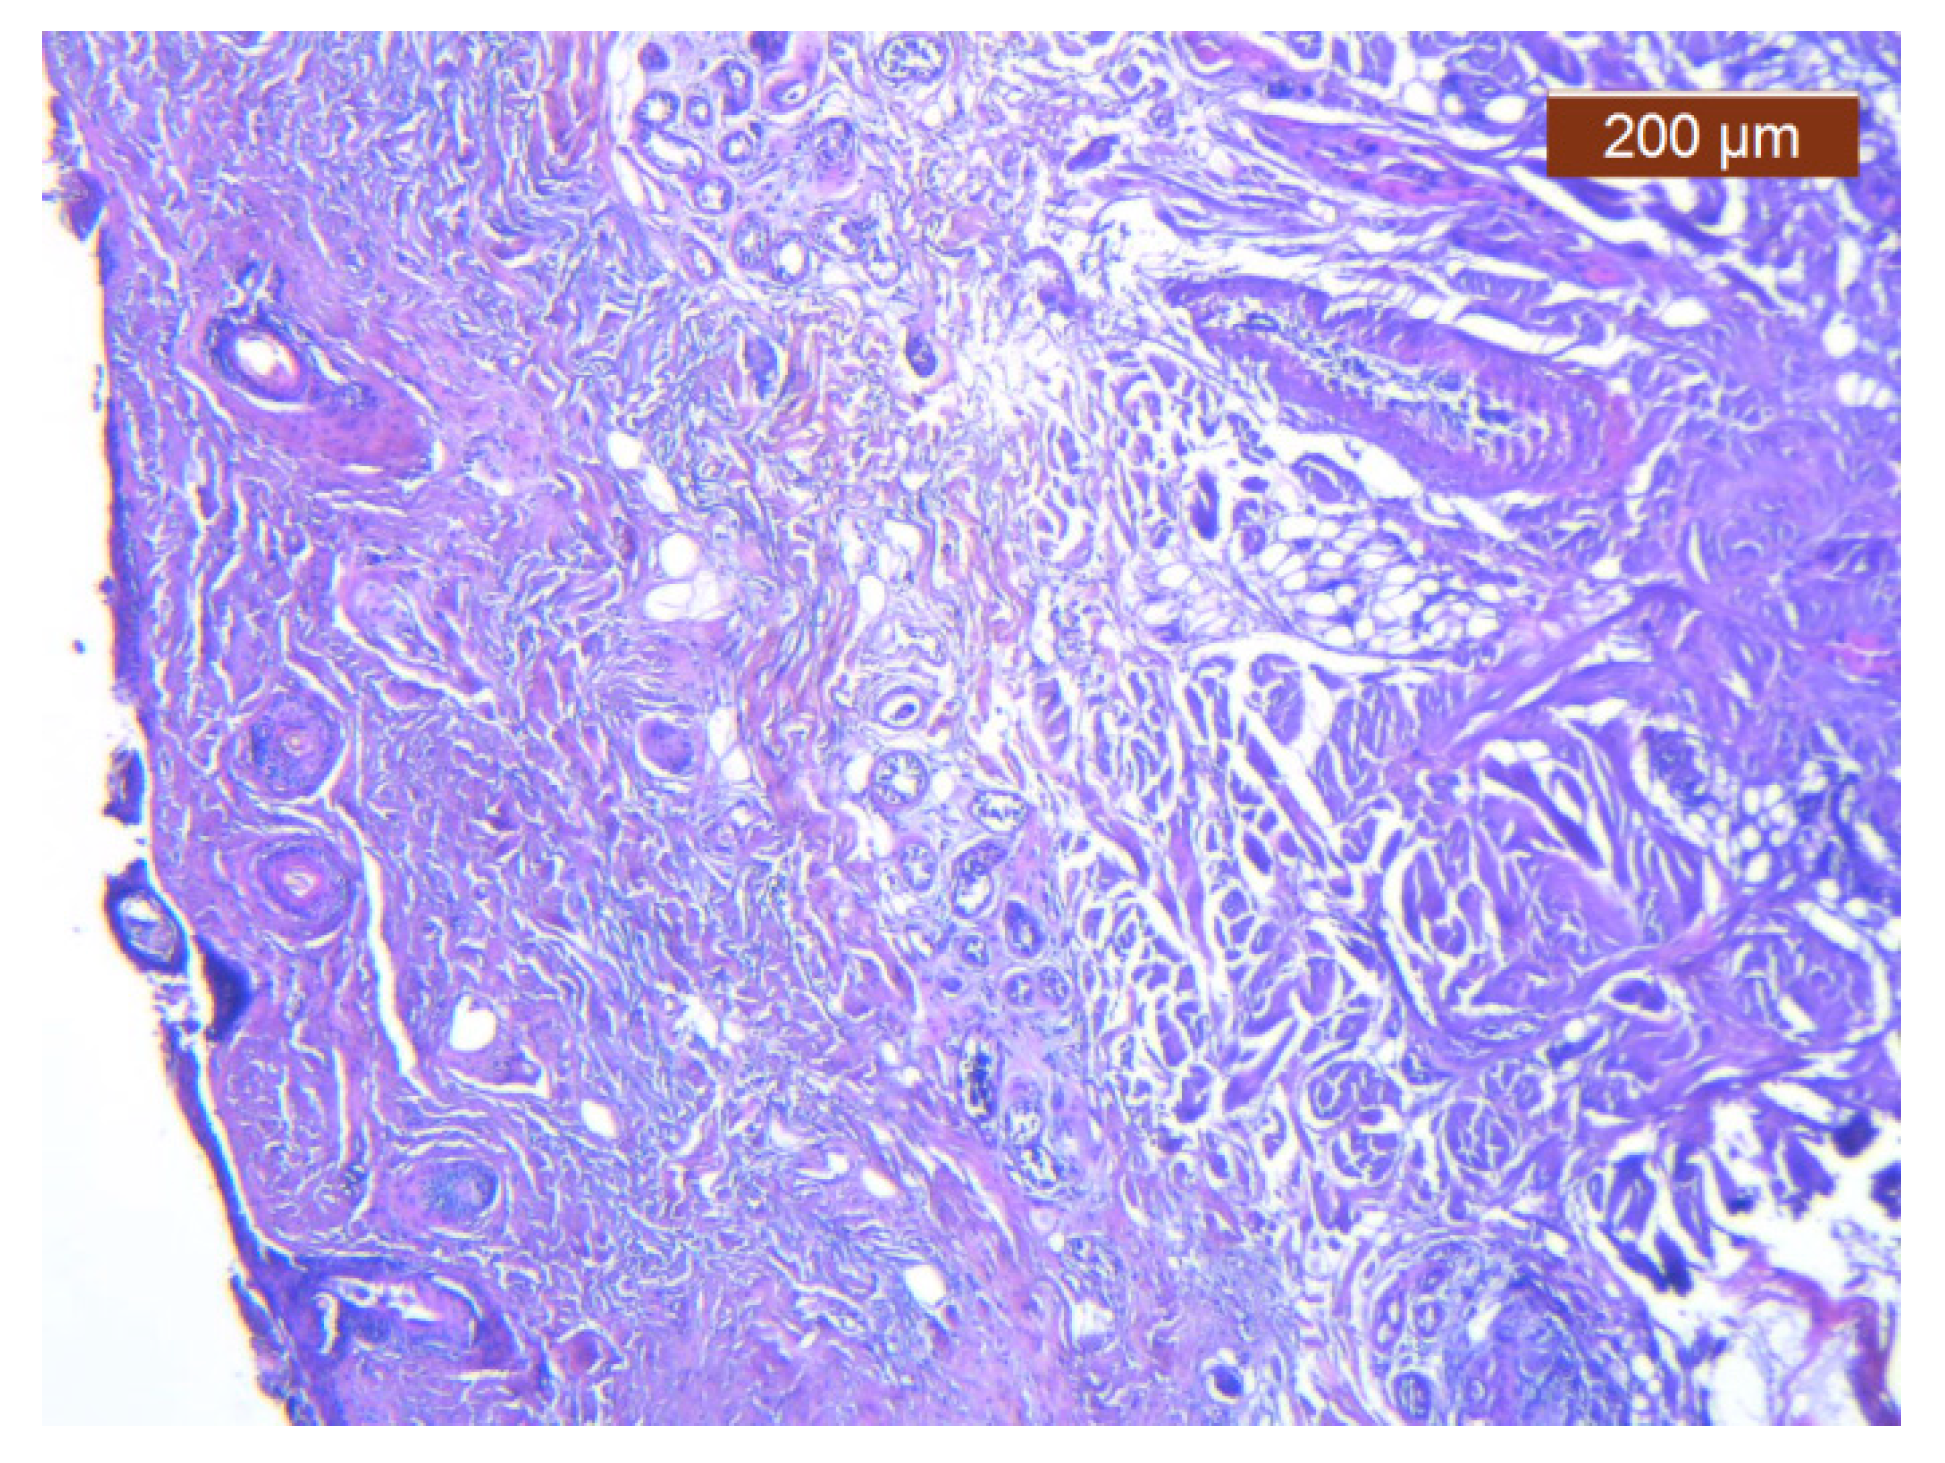

In this region, the arrangement of the SMAS layers from the superficial to the deep layers seemed very particular. Thus, in the immediate infradermal layer, we found strong collagen septa (Figure 10). The representation of blood vessels and muscle tissue at this level was almost absent.

Figure 10. Subcutaneous collagen thick septa. Collagen fibers (deep), blood vessels, and fat cells (middle alar area) (HE ×5).